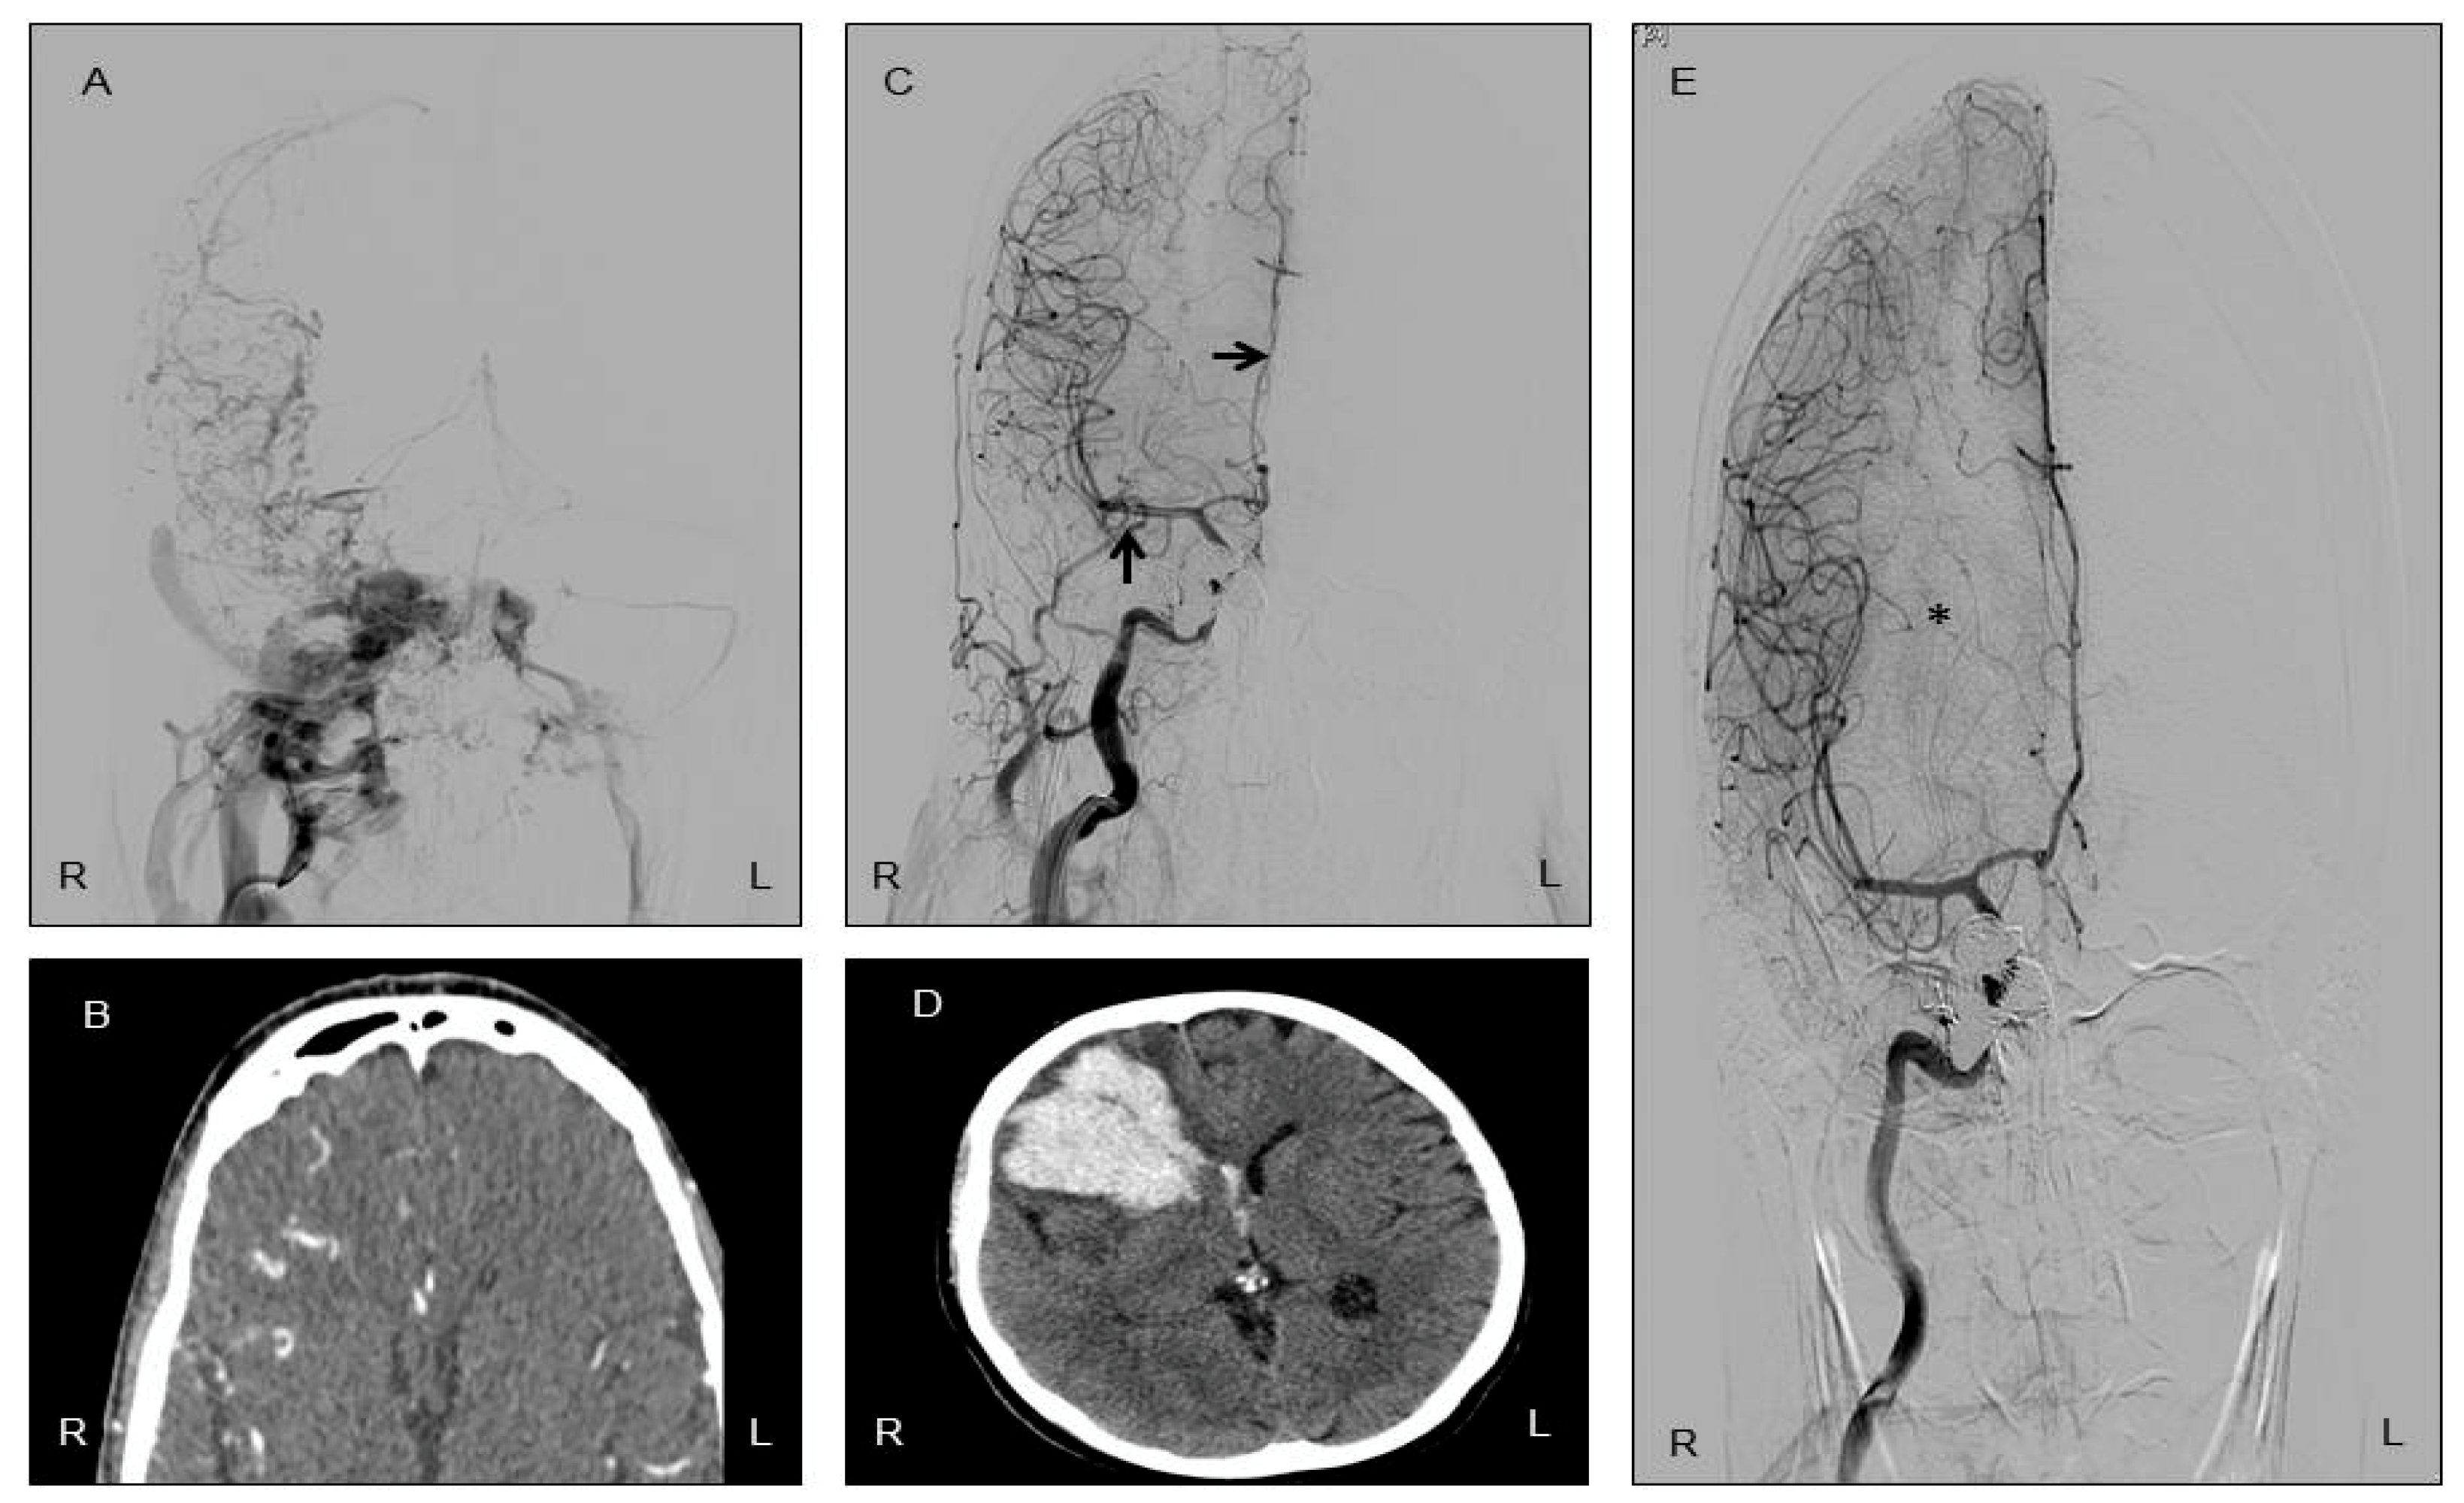

2. Case Presentation

| Author | Cloft et al. [14] | Cho et al. [15] | Present Case |

| Year of publication | 2002 | 2011 | 2025 |

| Age | 74 years | 48 years | 48 years |

| Sex | Female | Male | Female |

| Interval from CCF closure to ICH | 40 h | 24 h | 12 days |

| Side of hemorrhage | Left basal ganglia | Right parietal lobe | Right frontal lobe |

| Result | Deceased | Recovery | Recovery |